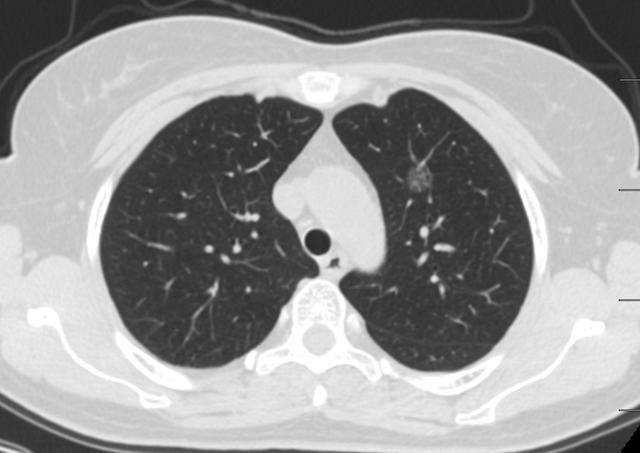

图1、2004年

图2、3 2008年1月10日

图4 2015年4月29日

图5、6 2020年5月15日

漫长的16年,一个纯磨玻璃结节从原位腺癌缓慢正常到浸润性腺癌早期阶段(影像估测),所以说纯磨玻璃结节是不可怕的,可以安心随访,到合适的时机手术完全来得及,不要上来动不动就手术,动不动就消融!